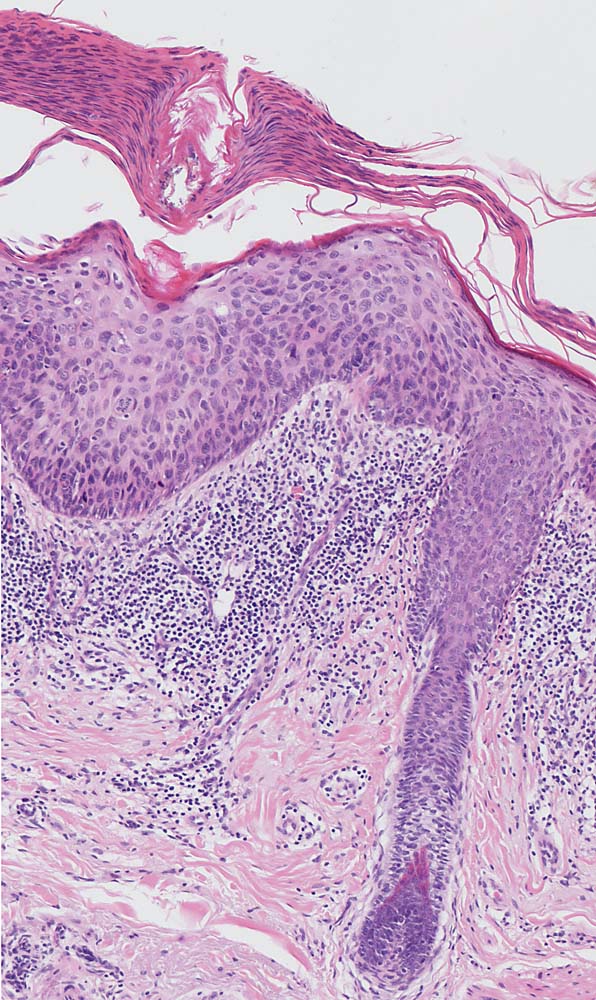

Solare Keratose bowenoider Typ

Hyper-parakeratotisch verhornende akanthotisch verbreiterte Epidermis. Dysplasie des Plattenepithels (vergrösserte hyperchromatische Zellkerne) auf der gesamten Epithelbreite unter Aussparung des Follikelepithels. Bandförmiges Entzündungsinfiltrat in der dermoepidermalen Junktionszone.

Aktinische Keratose der Wangenhaut.